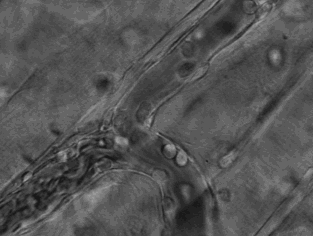

研究者从小鼠实验中发现,缺失TNF-α的小鼠对甜咸酸鲜等味道具有正常的反应,但对于苦味的反应敏感程度大幅降低。研究结果表明,TNF-α作用于口感神经部位。